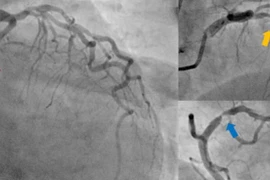

Bệnh nhân 77 tuổi ngưng tim sau nhồi máu cơ tim được cấp cứu kịp thời, hồi phục sau can thiệp mạch vành toàn diện tại Quảng Nam.